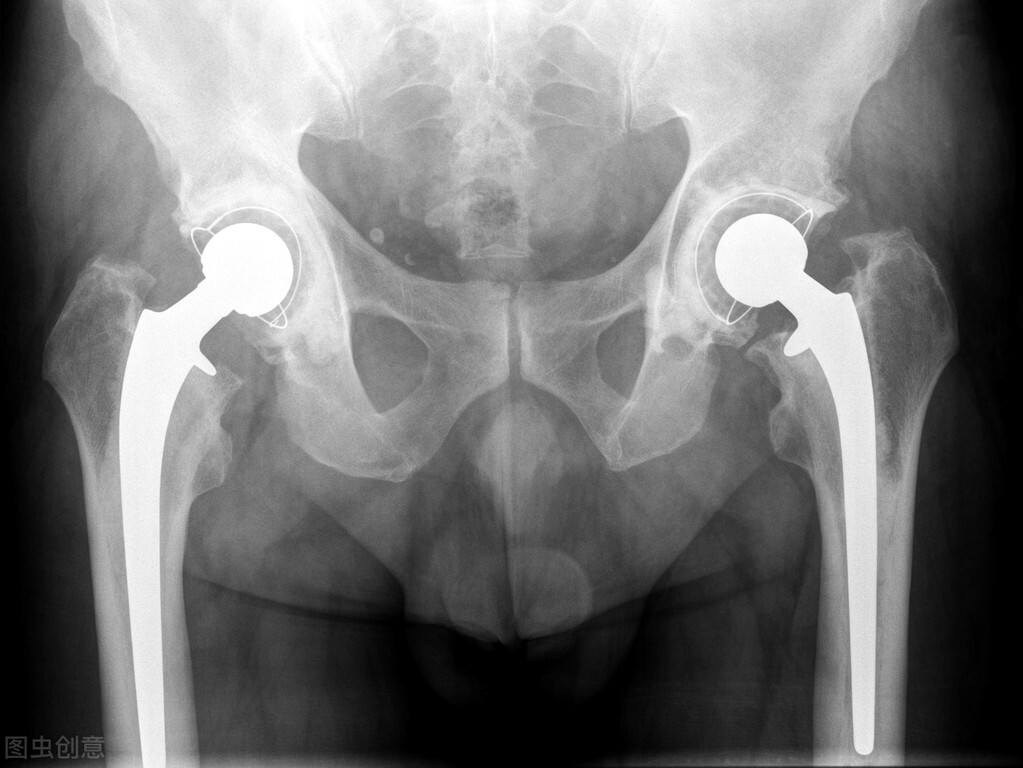

人工髋关节多应用于以下疾病:髋关节骨折、各种原因引起的股骨头坏死、类风湿或强直性脊柱炎引起的髋关节强直、重度的髋关节骨性关节炎。

人工髋关节包括三个组成部分:髋臼、球、柄。通常髋臼的外壳由金属制成而内衬为塑料或整个髋臼为塑料。当金属球与髋臼连接后,新的髋关节又可以进行光滑而没有摩擦的运动了。